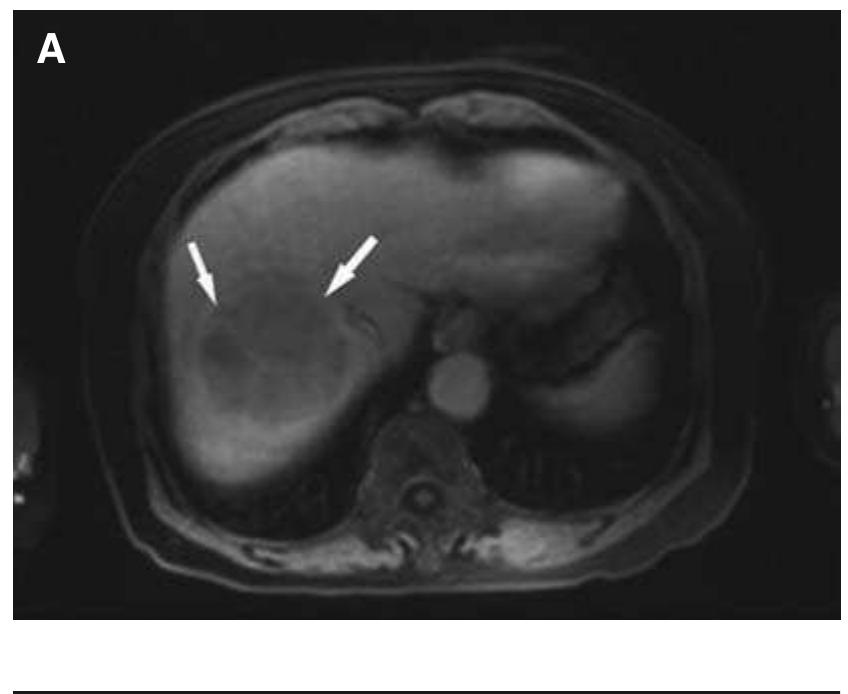

The knee is an anatomically and biomechanically complex joint. Few studies have been published reporting the type and frequency of knee injuries. However, this information that may help to prevent, diagnose, and treat knee joint injuries.... more